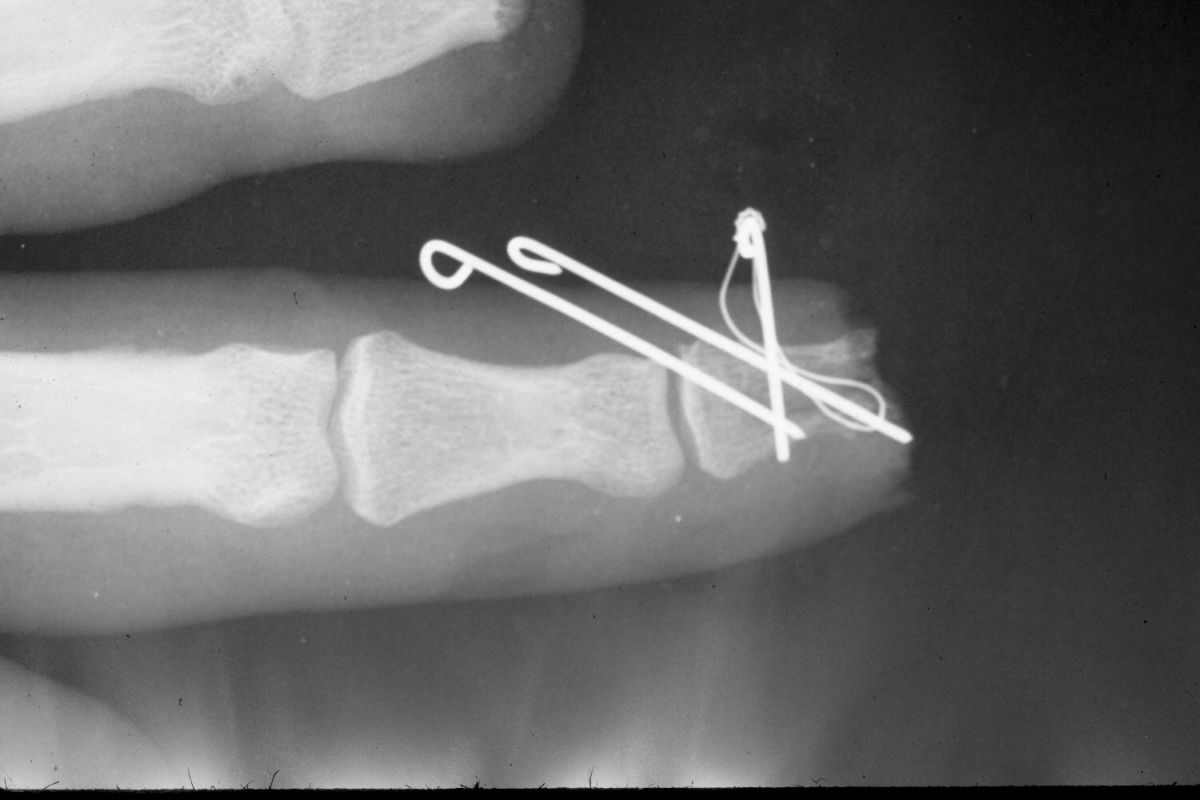

| Case

3. This gentleman sustained partial amputations of all fingers in an industrial press. His index finger was the only digit with a potentially salvageable fingertip. |

| Distal phalanx

fracture stabilization. Pins were placed to protrude

proximally in anticipation of flap cover. |